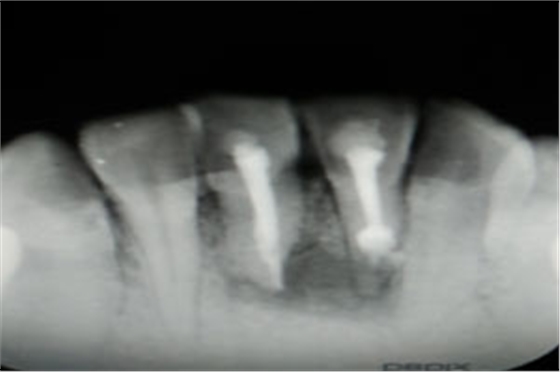

圖2.術(shù)前的根尖片影像、31根管治療已做,欠填少許。31、41根尖有橢圓形陰影,未見明顯骨白線。